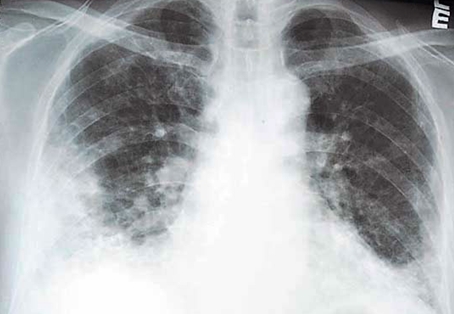

谁干的17岁少年的肺被炸成爆米花

17岁少年的肺被炸成爆米花国外已被禁许多人还在被它毒害中国人注意了

险些造成肺部完全损毁,健康严重受损,症状和"爆米花肺"有些类似,呼吸

险些造成肺部完全毁损,其病症与"爆米花肺"类似